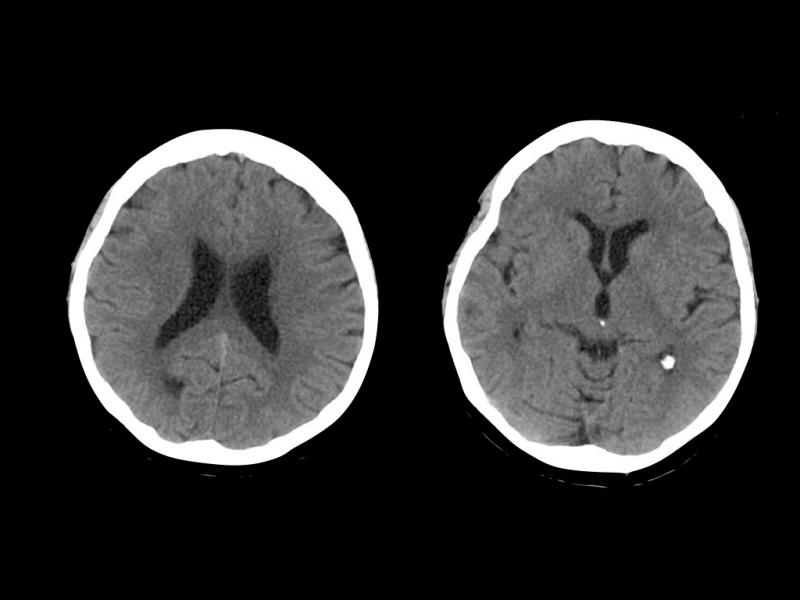

The most frequent locations of intracerebral haemorrhage were the basal ganglia/putamen, lobar, and thalamus. Several patients recorded an intracerebral haemorrhage score of 0 to 2, and many of them experienced poor neurologic outcomes, with a Modified Rankin Scale of 4 to 5 or even death.